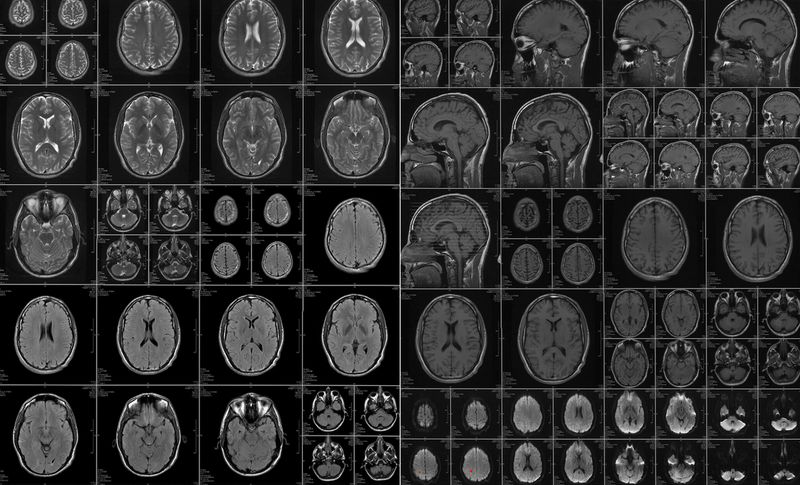

In 2010,my older brother had a stroke that was induced by some stress he was going through at the time. I was fresh out of school and on a “gap” year in China and Thailand. My brother had visited me a week before this happened and I was shaken by the news when I heard. He was fortunate that he was young and was able to recover quickly from the ordeal. It took 19 years to realize how fragile life was.